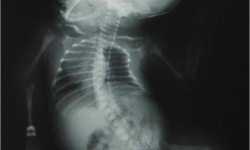

Dysplasia Epiphysealis Punctata

Fig 2: Both Ankle Lat. of a another patient